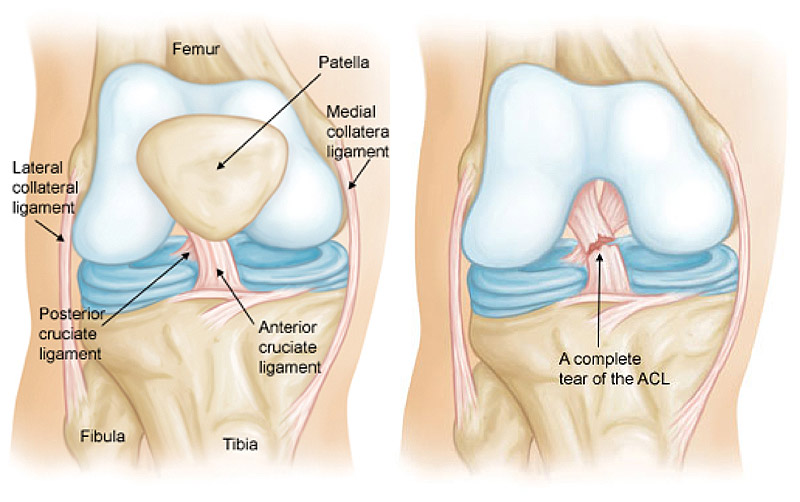

One of the more serious knee injuries an athlete can sustain is a tear of the anterior cruciate ligament, more commonly known as the ACL. Tearing of the ACL is usually seen in athletes playing high-contact or collision sports—however this is not a requirement for the injury. An ACL tear usually occurs when an athlete plants their foot, and twists, usually hearing a popping sound in their knee at the time of injury.

When the ACL is torn, another injury may be present, such as a torn meniscus and/or medical collateral ligament (MCL), a torn lateral collateral ligament (LCL), or a torn posterior cruciate ligament (PCL).

An ACL is: A cruciate ligament of the knee that attaches the front of the tibia with the back of the femur and functions especially to prevent hyper-extension of the knee.

An MCL is: A collateral ligament on the inside of the knee that serves as a stabilizer for the joint and supports the function of the knee.

ACL Tear (Left) and ACL Construction (Right)

- An ACL reconstruction is performed when the ligament is completely torn.

- When the ACL is not completely torn, a repair may be possible.